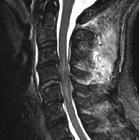

displaced unilateral facet fracture of cervical spine can lead to spinal cord injury: a report of two cases. Magnetic resonance imaging using a sagittal short T1 inversion recovery (STIR) sequence and b axial T2 weighted image at C5/6 at re-admission shows disc injury and spinal cord compression by a posterior epidural mass accompanied by an intramedullary signal intensity change at this level. Prevertebral soft-tissue edema, injury of the interspinous ligament, and a narrowed canal also are evident. There is no flow void in right vertebral artery on axial T2 weighted image, suggesting vertebral artery injury

Cervical

Spine MRI of patient with SCI: C4 fracture and dislocation, spinal cord compression